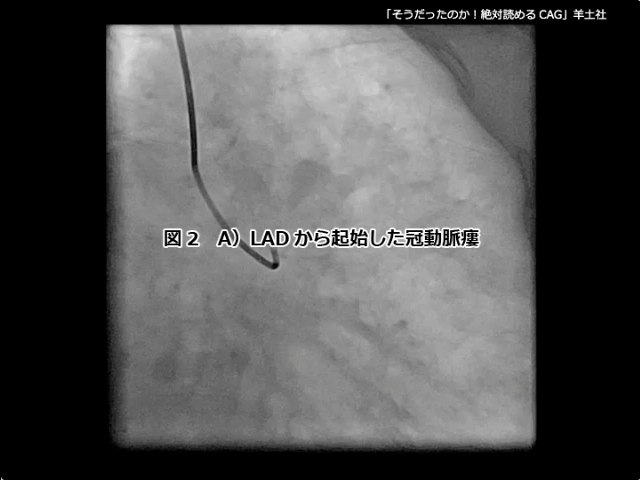

第5章-1 急性冠症候群の造影所見